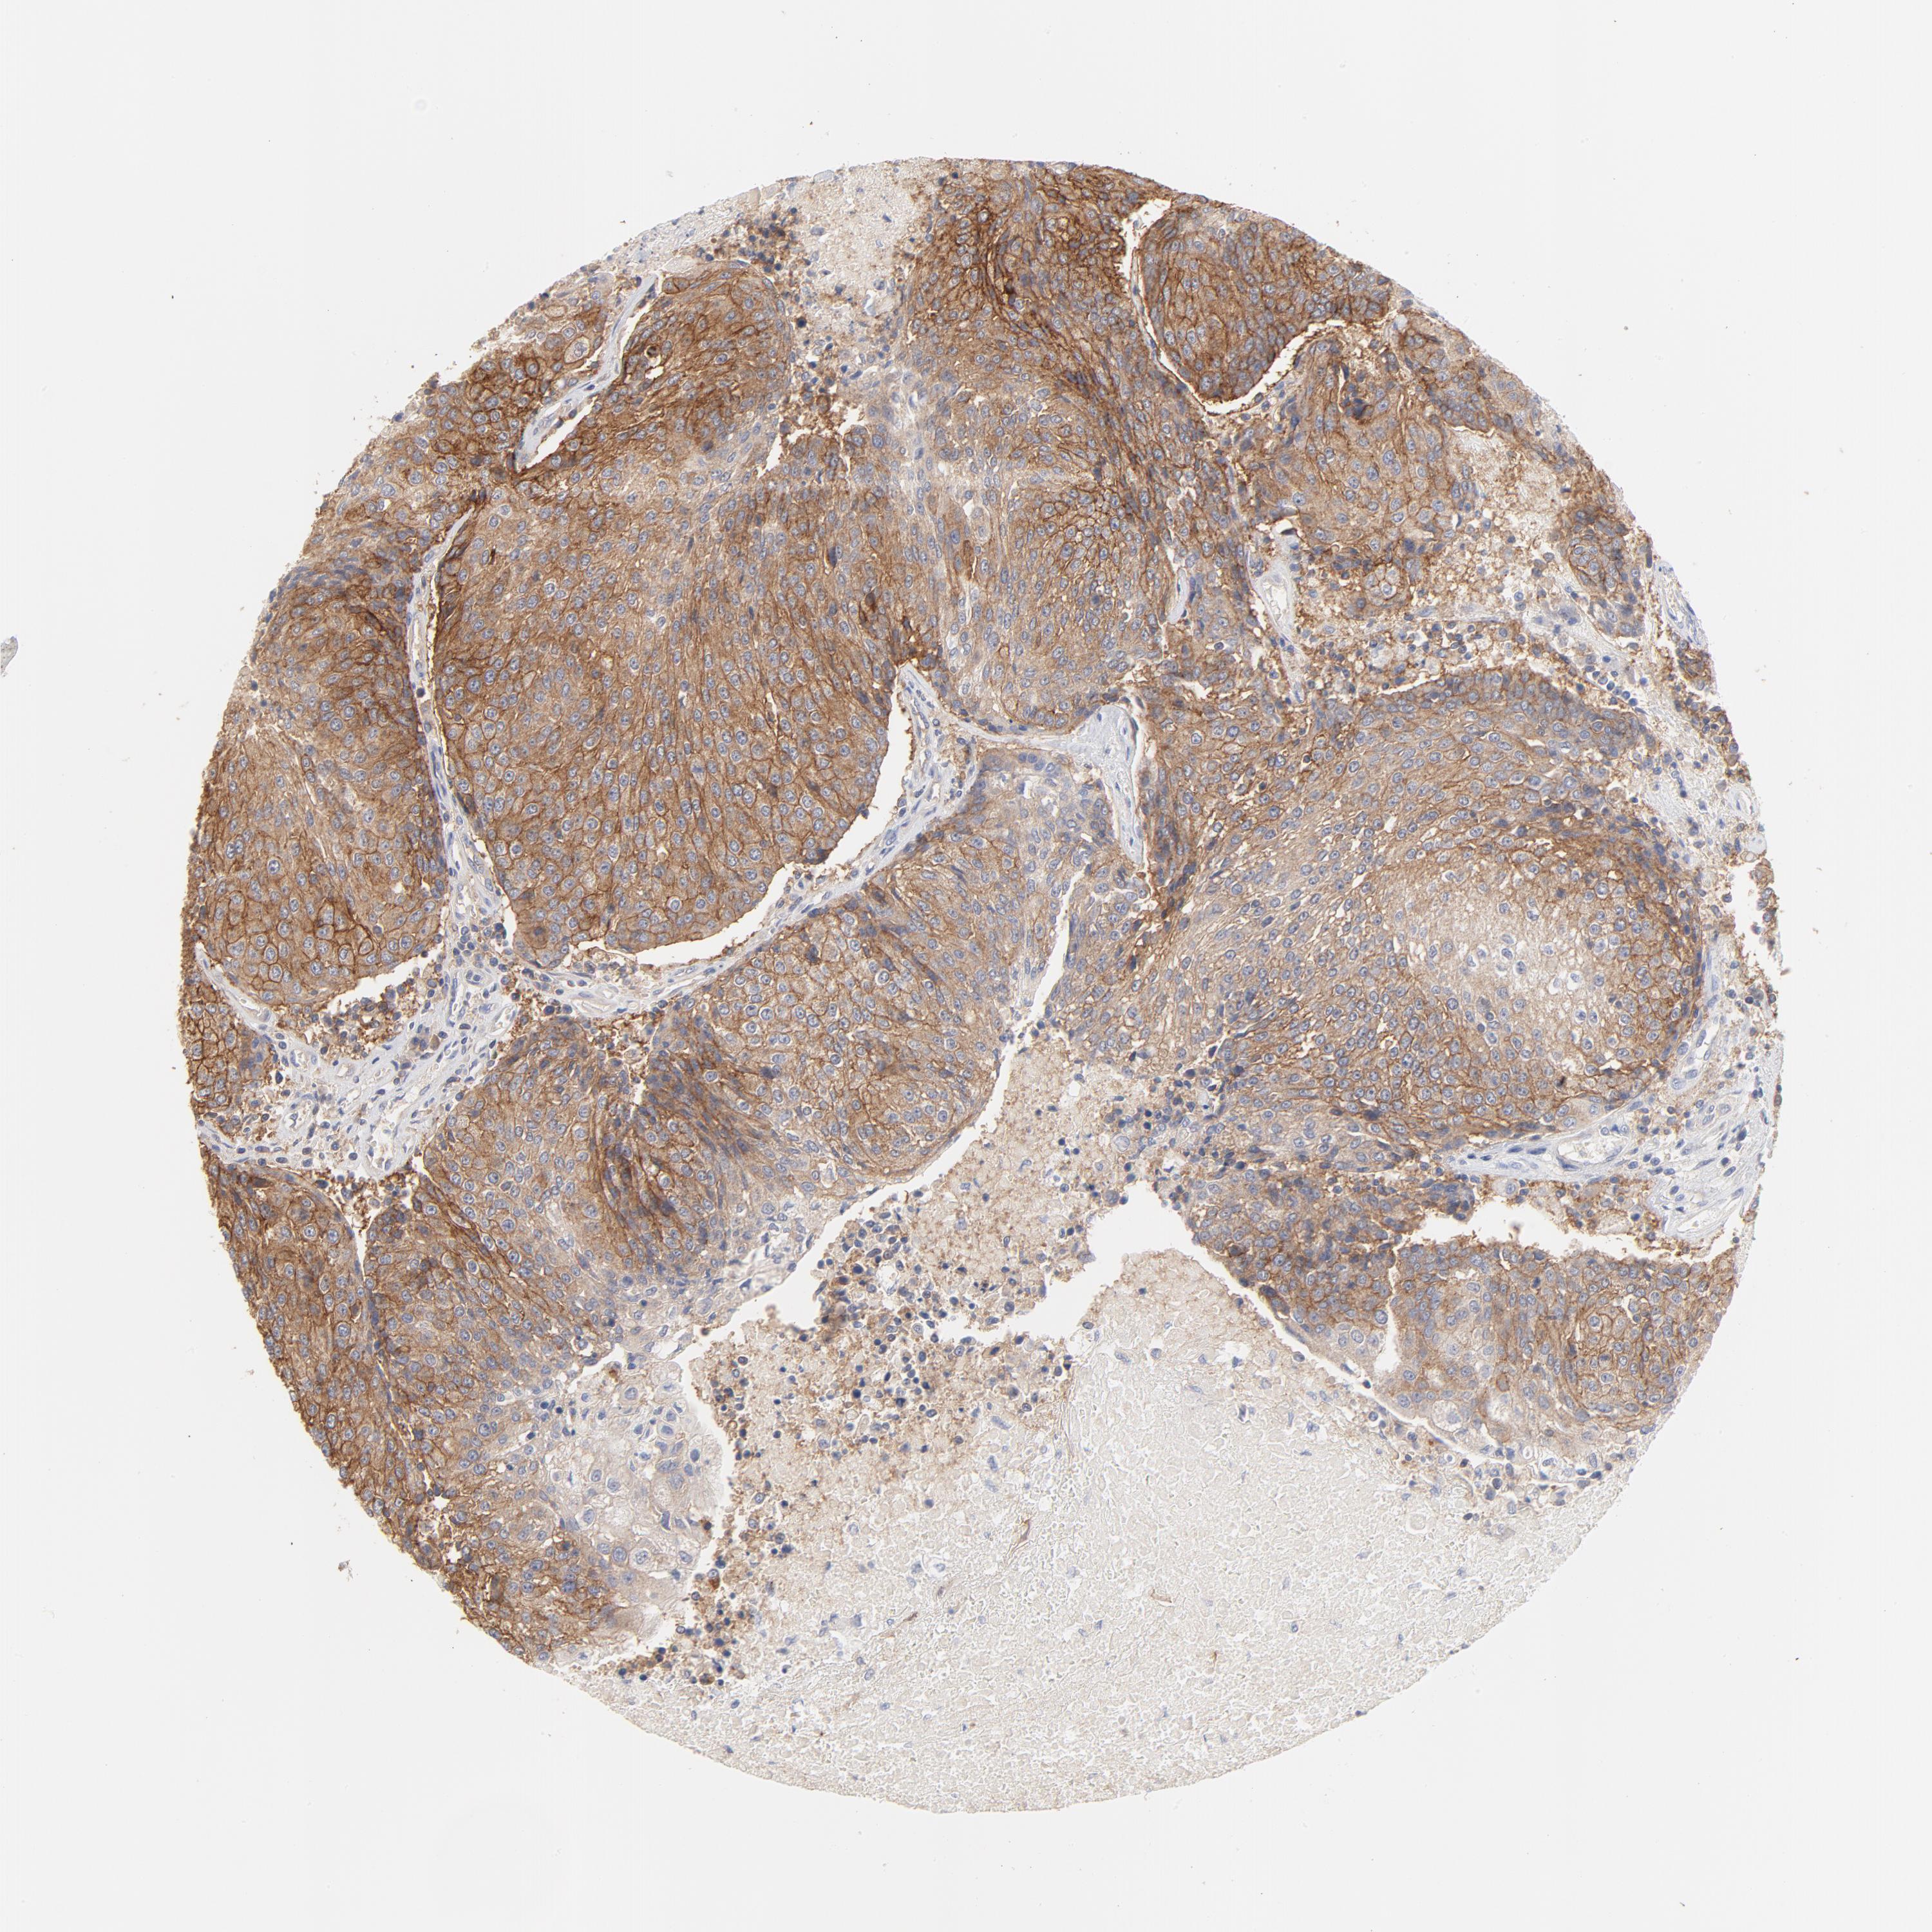

UROTHELIAL CANCER - Protein expressioni

A mouse-over function shows sample information and annotation data. Click on an image to view it in a full screen mode. Samples can be filtered based on level of antibody staining by selecting one or several of the following categories: high, medium, low and not detected. The assay and annotation is described here.

Note that samples used for immunohistochemistry by the Human Protein Atlas do not correspond to samples in the TCGA dataset.

Antibody stainingi

Antibody staining in the annotated cell types in the current human tissue is reported as not detected, low, medium, or high, based on conventional immunohistochemistry profiling in selected tissues. This score is based on the combination of the staining intensity and fraction of stained cells.

Each image is clickable and will lead to virtual microscopy that enables deeper exploration of all samples and also displays staining intensity scores, fraction scores and subcellular localization as well as patient and tissue information for each sample.

Antibody HPA003591

Antibody HPA003639

Staining

High

Medium

Low

Not detected

Intensity

Strong

Moderate

Weak

Negative

Quantity

>75%

75%-25%

<25%

None

Location

Nuclear

Cytoplasmic/membranous

Cytoplasmic/membranous,nuclear

Urothelial carcinoma, High grade

Urothelial carcinoma, Low grade